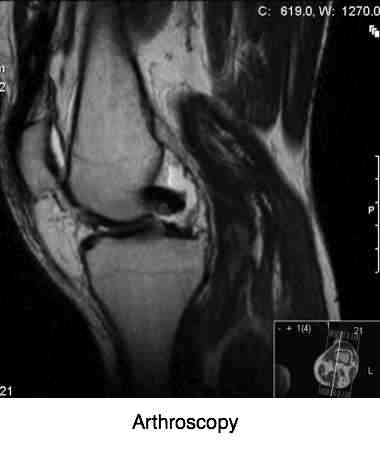

4 orthopedic tests were positive. The Drop Home, Medial McMurrays, MCL test and Clarke's test. All of which was a bit confusing: what was the primary source of pain? Most obvious was a painful click when straightening the knee with McMurray's test.

The MRI scan was not pretty. The medial meniscus was badly damanged.

ARTHROSCOPY KNEE SURGERY ...